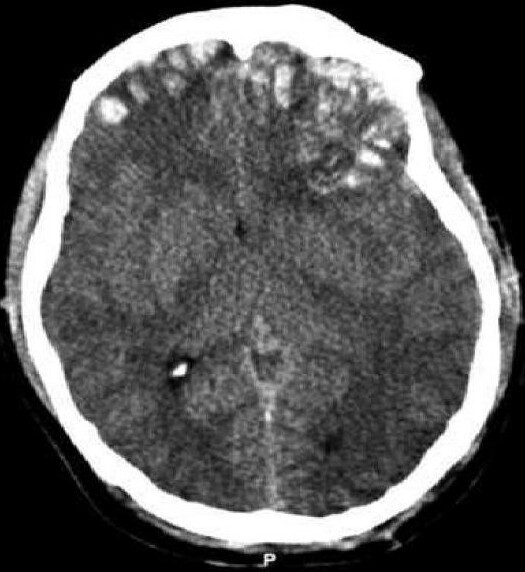

A diagnosis is confirmed using brain imaging, most commonly a CT scan. An MRI scan may be used in selected cases. Anyone who has suffered a significant head injury should seek medical attention.